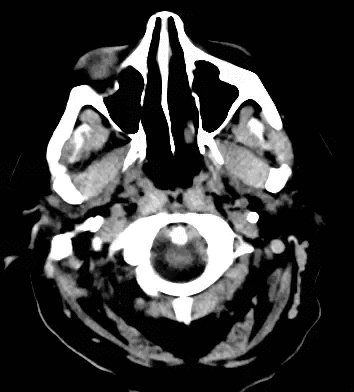

79 year old male with headaches, ataxia, falls, and difficulty urinating. What's the diagnosis?

Diagnosis: Ventriculomegaly secondary to Normal Pressure Hydrocephalus